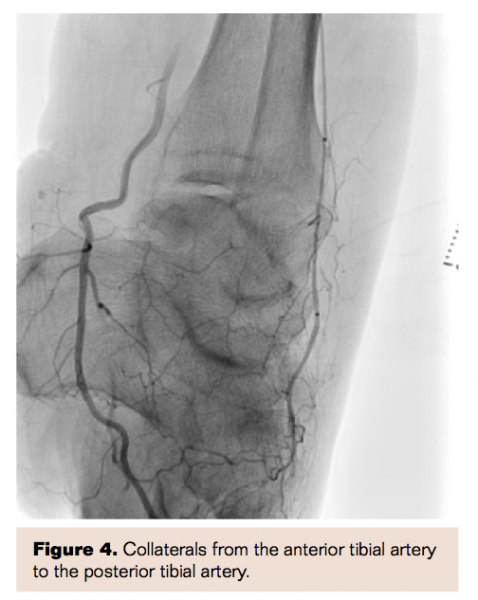

Following the intervention, the patient had excellent revascularization of the left SFA and the AT, which provided excellent collaterals to the PT (functional 2-vessel run-off to the lower extremity) (Figures 3 and 4. If the patient has further symptoms or critical limb ischemia, we will reassess with another ABI and consider opening the PT in retrograde fashion.